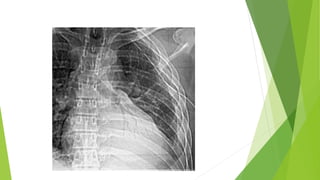

Signo del BroncogramaAéreo:  La silueta cardíaca a menudo oculta la patología del lóbulo inferior izquierdo en las radiografías AP y PA  El signo del broncograma aéreo superpuesto a la silueta cardíaca es el signo definitivo de consolidación en el lóbulo inferior izquierdo

• 10.

Broncograma Aéreo: - Signode localización, que excluye patología pleural o mediastínica, asegurando que la lesión al parénquima pulmonar, afectados los alvéolos, por lo tanto, siempre es indicativo de condensación pulmonar